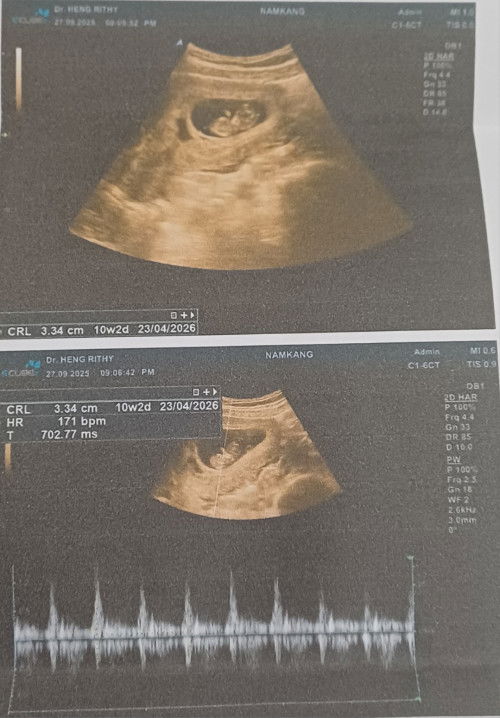

10week ค่ะแม่